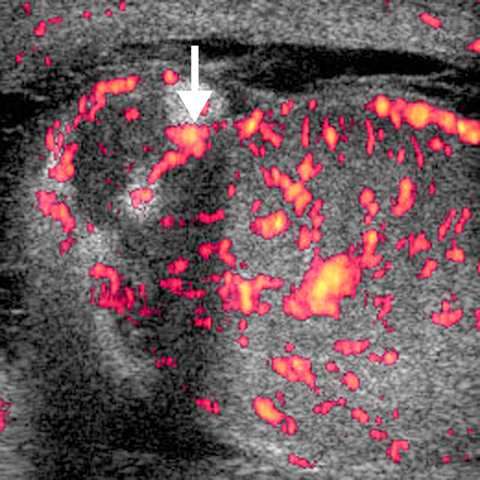

Edpididymo-orchitis [2 of 2]